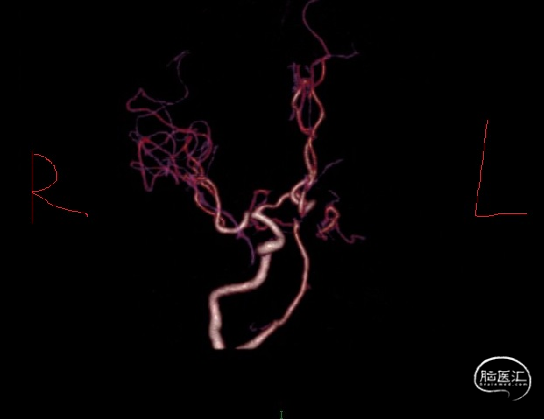

术前CTA:左侧颈内动脉、椎动脉颅内段、大脑中动脉未见显影,左侧大脑半球远端分支血管较对侧明显稀疏。

术前讨论:患者为醒后卒中,发病时间已超过静脉溶栓时间窗,未予静脉溶栓治疗。急诊CTA提示左侧颈内动脉、左侧大脑中动脉闭塞,ASPECTS 评分8分,尚未出现大面积低密度灶改变,CTP提示mismatch 为5.8,有明确的手术取栓指征。患者为高龄男性,既往有“高血压病”“脑梗死”病史,未规律服药治疗,无房颤及心脏瓣膜病病史,心源性栓塞可能性小,考虑动脉粥样硬化性狭窄继发血栓形成可能性大。

急诊DSA:主动脉弓造影提示LICA闭塞,RICA代偿差。

急诊DSA:LICA闭塞,LICA起始部次全闭塞。

急诊DSA:微导管于LICA-C2段造影见血栓近端所在,明确患者为LICA起始段次全闭塞合并远端栓塞的串联病变。